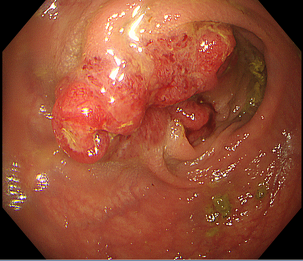

内視鏡下ステント留置術

消化管の狭くなっている部分に対してステント(筒のようなもの)を挿入し狭窄部を広げる治療になります。

主に癌などの悪性腫瘍の狭窄に対して行う治療で、切除不能狭窄の症状緩和目的や腸閉塞症状を伴う狭窄の緊急手術回避目的で行います。